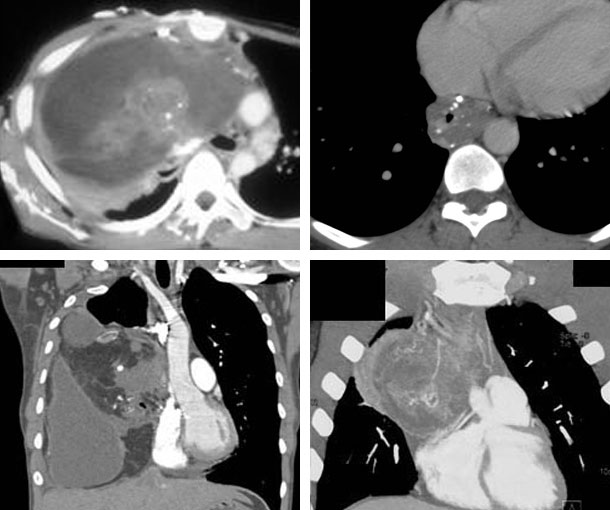

Mediastinal Teratoma CT Findings

- Well-demarcated mediastinal mass

- Heterogeneous

- Lobulated structure

- Cystic areas with fat or fluid contents

- Areas of dense calcifications

- SVC obstruction